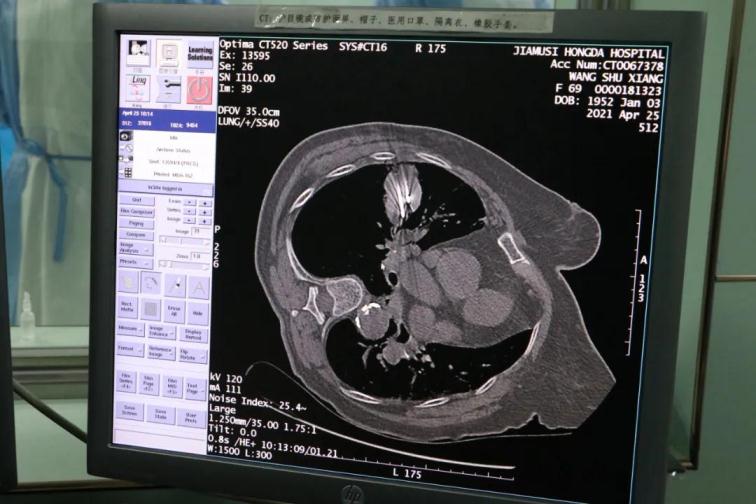

為了提高CT影像下肺腫瘤定位的精準(zhǔn)度,術(shù)前胸外科團(tuán)隊(duì)聯(lián)合CT影像科趙文禮主任和董明鑫醫(yī)師詳細(xì)研究了肺CT定位方案,采取國(guó)際上先進(jìn)的CT網(wǎng)格定位法,對(duì)肺腫瘤精確定位,定位精度可達(dá)5mm以內(nèi)。經(jīng)過團(tuán)隊(duì)合作充分準(zhǔn)備后對(duì)肺癌實(shí)施了氬氦刀穿刺治療,微創(chuàng)穿刺針孔3mm,局麻鎮(zhèn)痛,分段治療40分鐘。病人全程在韋文康護(hù)士長(zhǎng)護(hù)理團(tuán)隊(duì)心肺監(jiān)測(cè)下進(jìn)行,確保了手術(shù)安全。

氬氦刀治療后即刻CT評(píng)價(jià)肺腫瘤核心密度下降,手術(shù)后5天CT評(píng)價(jià)肺癌與周圍正常肺組織對(duì)比,水腫帶形成,癌組織出現(xiàn)壞死。治療取得了良好效果。遠(yuǎn)期效果需要繼續(xù)隨訪觀察。病人手術(shù)后1周無并發(fā)癥痊愈出院。